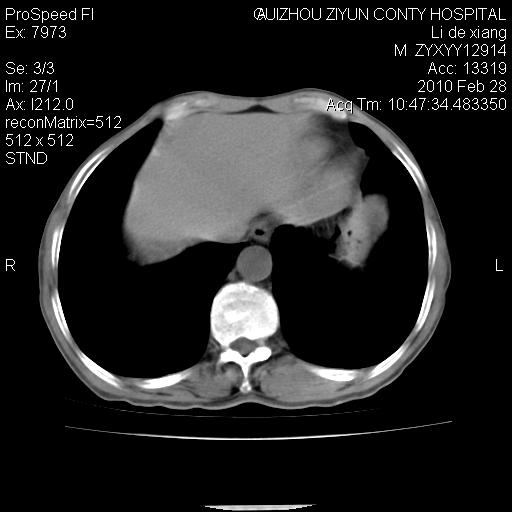

标题: CT24776:男 71Y 咳嗽咳痰胸痛两月,伴声音嘶哑。 [打印本页]

标题: CT24776:男 71Y 咳嗽咳痰胸痛两月,伴声音嘶哑。

纵膈淋巴结肿大 不除外占位性阻塞

左上叶支气管狭窄,阻塞性病变,肺门肿块,纵隔及肺门淋巴结增大,中央性肺癌

左肺中央型肺癌并阻塞性改变、纵膈 淋巴结转移